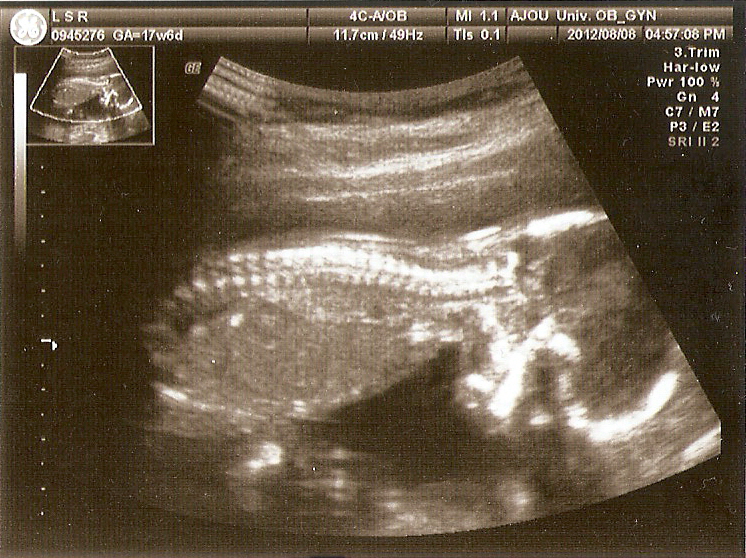

애기 초음파 사진 모음

초음파 사진이랑 입체 초음파 사진이랑은 차이가 크긴 하다.

하솔이 초음파 사진~~맘고생 했을때가 생각남...히히~~^^